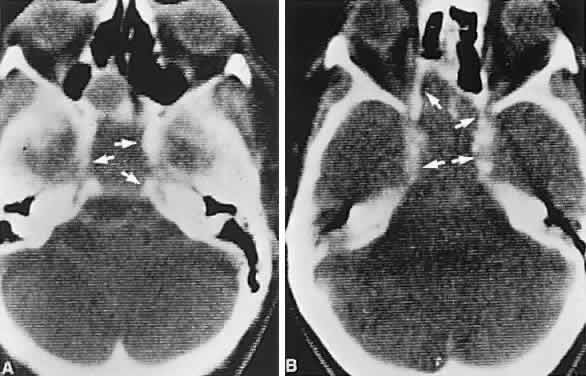

Clinical signs and symptoms include the following: acute onset of severe headache, often sickening frontal or retro-bulbar cephalgia, or other less disabling change in headache pattern; acute or rapidly progressing unilateral or bilateral (usually asymmetric) ophthalmoplegia due to rapid expansion into cavernous sinuses (see also Volume 2, Chapter 12); epistaxis or CSF rhinorrhea when the mass ruptures or erodes into the sphenoid sinus; complications of blood or necrosis debris in the CSF, with “pseudomeningitis”; rapid neurologic deterioration and obtundation, although patients need not be stuporous; and, greater or lesser degrees of hypopituitarism.62,63 Selective expansion laterally into the cavernous sinus may produce ophthalmoplegia without visual loss; selective expansion superiorly may produce visual loss without ophthalmoplegia. Almost without exception, enlargement of the sella is found even on plain skull film views; both CT and MRI detect fresh hemorrhage (Fig. 3), but MRI may fail to demonstrate acute hemorrhage unless specific sequences are employed (hemorrhage may be isointense on T1-weighted images and hypointense on T2-weighted images; in the subacute phase, extracellular methemoglobin should appear bright on both T1 and T2 sequences). Corticosteroid replacement and other supportive measures may be critical, and, in most instances, decompression through the sphenoid sinus is advisable, sooner rather than later. Bromocriptine has been suggested as a temporizing measure when signs and symptoms are modest and not progressing,64 and there are advocates65 for conservative management consisting of intravenous dexamethasone, so long as visual deficits are minimal or rapidly improve; otherwise decompressive surgery is required. Given the regularity with which pituitary apoplexy is often a delayed diagnosis, being confused with ruptured aneurysm or meningitis, for example, and that transsphenoidal surgery is a relatively simple undertaking, further procrastination in decompression of the compromised visual pathways is to be avoided.

Fig. 3. Neuroimaging of pituitary adenomas. A. Axial computed tomography (CT) section shows a round tumor mass filling the suprasellar cistern; ring enhancement (arrows) indicates subcapsular hemorrhage. B. Contrast-enhanced coronal CT section through a large invasive adenoma. Note encasement of the carotid artery (arrows) and the position of the middle cerebral artery above (arrowheads). C. Axial CT section shows lateral expansion into the cavernous sinuses (white arrows) and a necrotic cyst (black arrow). D. Subfrontal superior extent of the mass. Note the middle cerebral arteries. E. Magnetic resonance imaging of a large lobulated prolactinoma, with suprasellar extension. Note the distortion of the third ventricle (open arrows) and extension toward the temporal lobe (long arrow); the tumor has not involved the sphenoidal sinus (s). F. Chiasm (arrowheads) is draped on the superior surface of the tumor (TR, 550 milliseconds; TE, 26 milliseconds). G. Sagittal section shows suprasellar growth with the chiasm above (arrowheads); the sella (arrows) and sphenoidal sinus (s) are normal (TR, 850 milliseconds; TE, 26 milliseconds). H. Hyperintense signal (TR, 2000 milliseconds; TE, 60 milliseconds) indicates the partial cystic character. Sagittal (I) and axial (J) sections with head tilt to the right, in case of a large cystic adenoma with an interface level between newer blood (white arrow) and older blood (black arrow) (TR, 800 milliseconds; TE, 30 milliseconds). K. Signal difference is intensified (TR, 2100 milliseconds; TE, 80 milliseconds). L. Hemorrhage (bright signal, arrow) in a pituitary adenoma with headache and bitemporal field depressions. M. Without interventions, 2-month follow-up showed spontaneous involution, with normal pituitary gland (arrow), stalk, and chiasm.